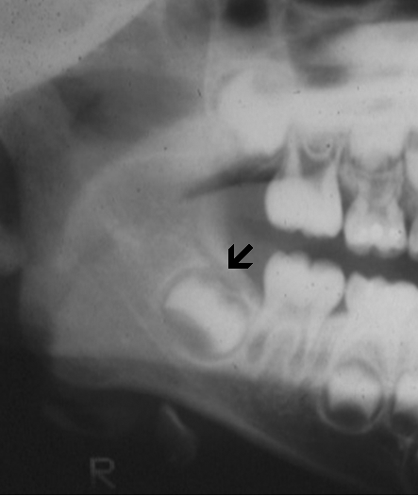

Panoramic radiography shows a radiolucent, multilocular mass that expanded the left ramus (A). It involves the ramus tooth #17 to #21 and also extends into the left condyle. The margin of the lesion is scalloped and non-sclerotic. No periosteal reaction is present. Some fine trabeculae are present but no radiodensity suggestive of mineralized content are present.